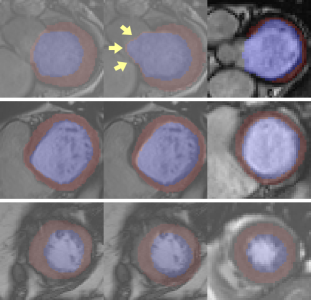

We notice that the Dice index of the LVM is significantly lower than that of the other parts. We believe that this is partly due to the variability of the ground-truth in UK Biobank as presented in Fig.3. This kind of variability influences both the learning and the evaluation of our method. The Dice index of LVM is most heavily affected. Indeed, on the one hand, LVM is more difficult to segment than LVC due to its shape. Ambiguity on the ground-truth makes the learning of the LVM segmentation even harder. On the other hand, LVM represents a small volume. The Dice index is hence more sensitive to errors in this structure. In general, not only for LVM, the variability in UK Biobank ground-truth reduces the performance for all structures in terms of Dice index. In contrast, the Hausdorff distance is much less sensitive to this variability, which also explains the better performance of our model.

Notice that the results reported in Table I are based on 3D volumes. To evaluate the performance of LVRV-net across different slices, given a structure (e.g. LVM), we also provide results for 5 evenly distributed levels from the slice + to the last slice on which the structure is present (Fig.4 Left). Group 1 (G1) is on top of the sub-stack and close to the base. Group 5 (G5) is close to the apex. Then we evaluate the segmentation performance of LVRV-net in terms of heart (defined as the union of LVC, LVM, and RVC) presence rate (Fig.4 Right), and 2D Hausdorff distance for 4 different structures (Fig.5).